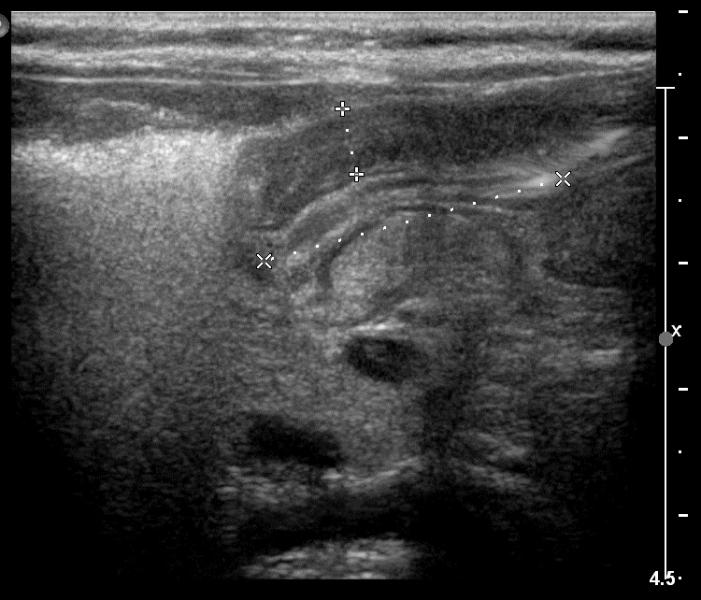

2-miesięczny chłopiec z chlustającymi wymiotami.

Przypadek 5: 2-miesięczny chłopiec z chlustającymi wymiotami.

Rozpoznanie: W badaniu usg - pogrubiała mięśniówka odźwernika, kanał odźwiernika szczelinowaty. Przerostowe zwężenie odźwiernika (pylorostenoza).